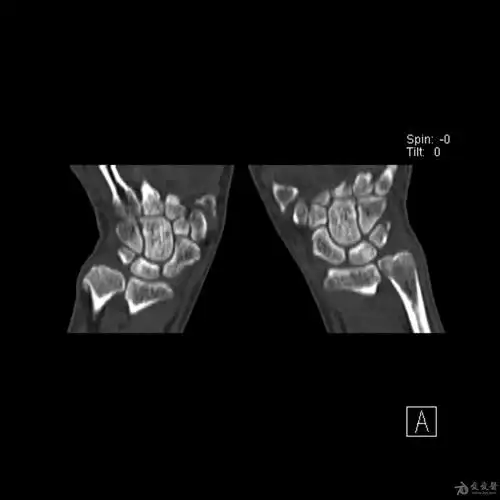

腕部三角骨骨折